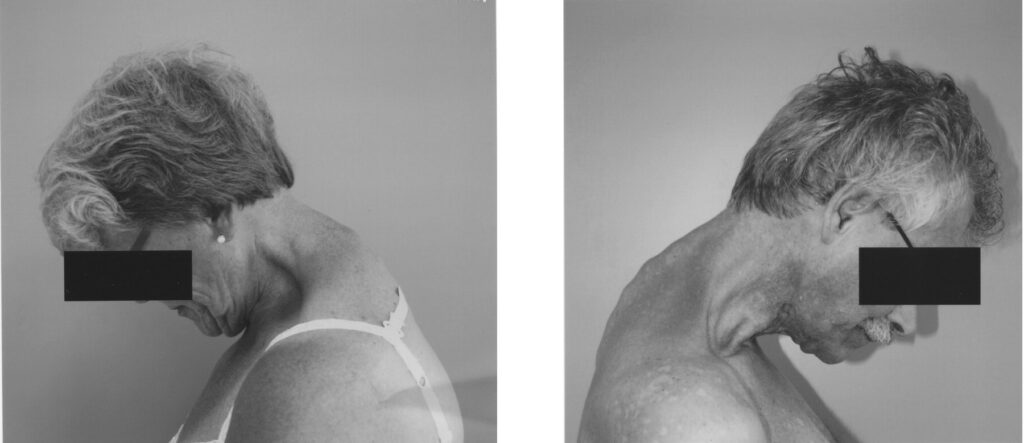

Drop Head Syndrome është një gjendje neurologjike ose muskulare e karakterizuar nga dobësi e rëndë e muskujve ekstensorë të qafës, që rezulton në pamundësi për të mbajtur kokën drejt. Kjo gjendje shkakton një përkulje, varje të plotë të kokës përpara, e cila përmirësohet përkohësisht kur pacienti e mbështet kokën me duar ose kur rri shtrirë.

3. Simptomat

Simptoma kryesore:

Koka bie përpara totalisht (flexion i theksuar cervikal).

Simptoma të tjera shoqëruese:

• Dhimbje qafe ose lodhje muskulare.

• Vështirësi për të parë drejt, sidomos përpara ose lart.

• Përmirësim i pozicionit të kokës kur pacienti shtrihet.

• Gjatë ecjes e pamundur të mbahet koka drejt.

• Probleme me gëlltitjen (dysfagia) ose frymëmarrjen në disa raste.

• Humbje force në sup dhe shpatulla (varësisht nga shkaku).